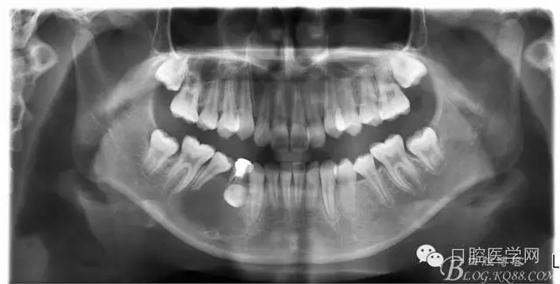

查:右側(cè)第二前磨牙第一乳磨牙恒尖牙頰側(cè)前庭溝隆起,捫有乒乓球感。曲斷及CT示:右側(cè)第二前磨牙第一乳磨牙恒尖牙根尖區(qū)有一囊腫,頰舌側(cè)骨板極薄,牙根無吸收,第二前磨牙牙根位于囊腫中,第一雙尖牙牙冠遠(yuǎn)中水平向阻生,牙冠位于囊腫中。經(jīng)協(xié)議:手術(shù)摘除創(chuàng)傷大,同意開創(chuàng)引流保守治療。

術(shù)后一個月 三個月 五個月 八個月 拔除第一雙尖牙后曲斷片: